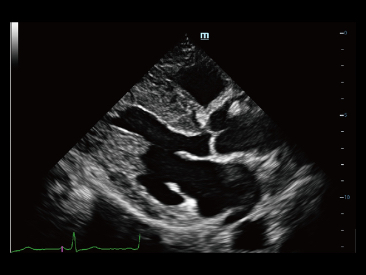

Seit der Gr├╝ndung des Unternehmens hat Mindray fortlaufend neue Wege zur Verbesserung der diagnostischen Zuverl?ssigkeit erforscht. Angetrieben von der revolution?rsten Technologie ZONE Sonography?, bringt die neue ZST+ Plattform von Resona 7 die Ultraschallbildqualit?t durch Zonenerfassung und Kanaldatenverarbeitung auf ein h?heres Niveau.

Dank der ZONE Sonography?-Technologie (ZST+) wird das B-Bild des Resona 7 ├╝ber die komplette Tiefe fokussiert, sodass keine Fokuspunkte mehr gesetzt werden m├╝ssen. Die Schall-Lauf-Geschwindigkeit (SSC) wird auf Knopfdruck individuell auf den Patienten angepasst, was die Darstellung von Organen, Grenzfl?chen und Gewebever?nderungen erheblich verbessert. Und dank der fortschrittlichen iFusion-Funktion k?nnen optional die Daten von Ultraschall-, MRT-und CT-Bildern synchronisiert werden.